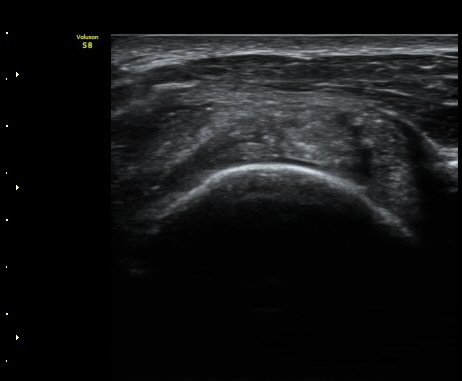

ŽÃÊÀÚ¸¦ ¾à°£ ´Ù¸®ÂÊ, ³»ÃøÀ¸·Î À̵¿ÇÏ´Ï °ß°©ÇÏ±Ù°Ç Ç¥Ãþ¿¡ ¸¹Àº ¾çÀÇ ¼ö¾×Àú·ù°¡ °üÂûµÈ´Ù(»çÁø 3).